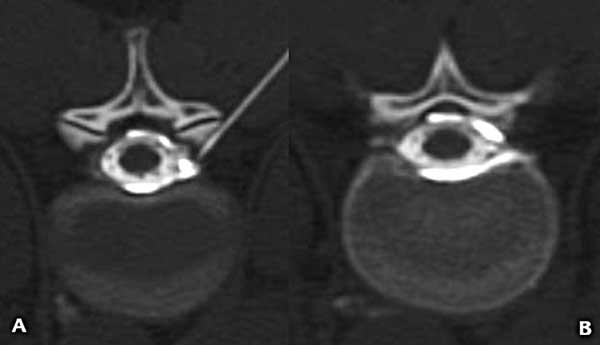

Luego de analizar las imágenes se decidió abordar el quiste radicular. En decúbito ventral se dirigió una aguja espinal 21G hasta el neuroforamen, inyectando 2 cm3 de lidocaína al 1% marcada con contraste yodado, se identificó, así, el llenado del componente extradural del quiste sin pasaje al saco tecal (Figura 4); comprobado esto, se inyectaron seguidamente 10 cm3 de sangre autóloga recientemente extraída a la paciente.

Figura 4. Mielo-TC. A) Corte axial donde se puede ver el extremo de la aguja en el neuroforamen y el medio de contraste que rellena el espacio peridural. B) Corte axial inmediatamente por encima de la figura 3 en el que se observa el medio de contraste concentrado en el espacio peridural sin pasaje al interior del saco tecal.